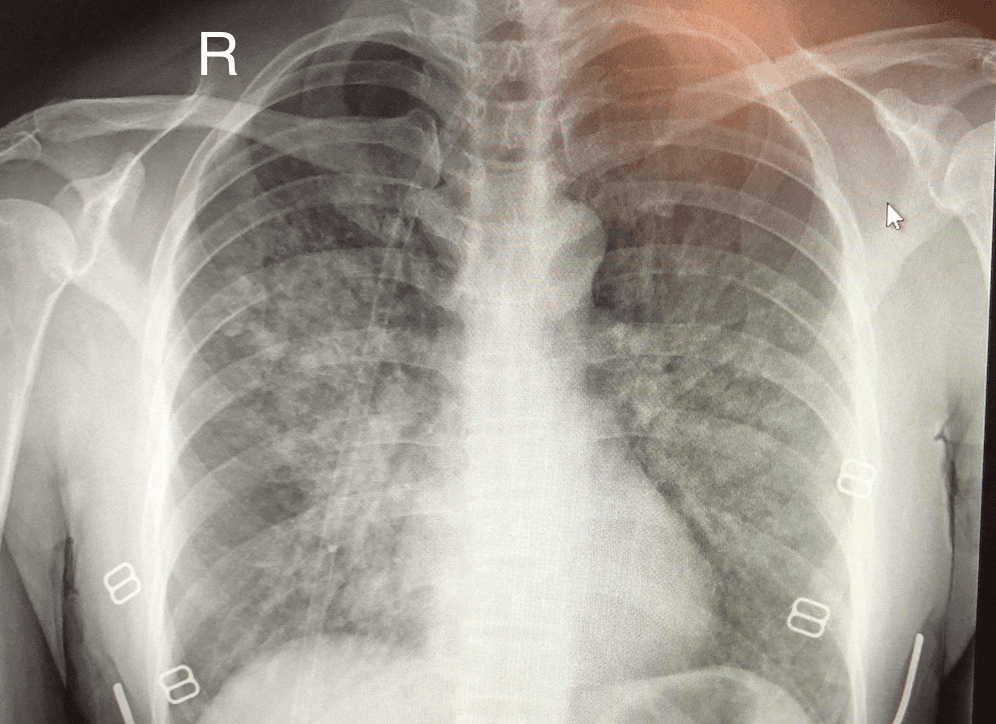

High-altitude pulmonary edema (HAPE) is a life-threatening form of non-cardiogenic pulmonary edema that occurs in otherwise healthy people at altitudes typically above . However, cases have also been reported between in more vulnerable subjects. Classically, HAPE occurs in persons normally living at low altitude who travel to an altitude above 2,500 meters (8,200 feet). Re-entry HAPE is also an entity that has been described in persons who normally live at high altitude but who develop pulmonary edema after returning from a stay at low altitude. It is severe presentation of altitude sickness. There are many factors that can make a person more susceptible to developing HAPE, including genetic factors, but detailed understanding is lacking and currently under investigation. HAPE remains the major cause of death related to high-altitude exposure, with a high mortality rate in the absence of adequate emergency treatment. Physiological and symptomatic changes often vary according to the altitude involved. The Lake Louise Consensus Definition for high-altitude pulmonary edema has set widely used criteria for defining HAPE symptoms. In the presence of a recent gain in altitude, the presence of the following: Symptoms: at least two of: Shortness of breath at rest Cough Weakness or decreased exercise performance Chest tightness or congestion Signs: at least two of: Crackles or wheezing (while breathing) in at least one lung field Central blue skin color Tachypnea (rapid breathing) Tachycardia (rapid heart rate) Acute mountain sickness and high altitude cerebral edema may also be present in conjunction with HAPE, however these symptoms may be subtle or not present at all. The most reliable sign of HAPE is severe fatigue or exercise intolerance, especially in a climber that was previously not displaying this symptom. There are multiple factors that can contribute to the development of HAPE, including sex (male), genetic factors, prior development of HAPE, ascent rate, cold exposure, peak altitude, intensity of physical exertion, and certain underlying medical conditions (e.